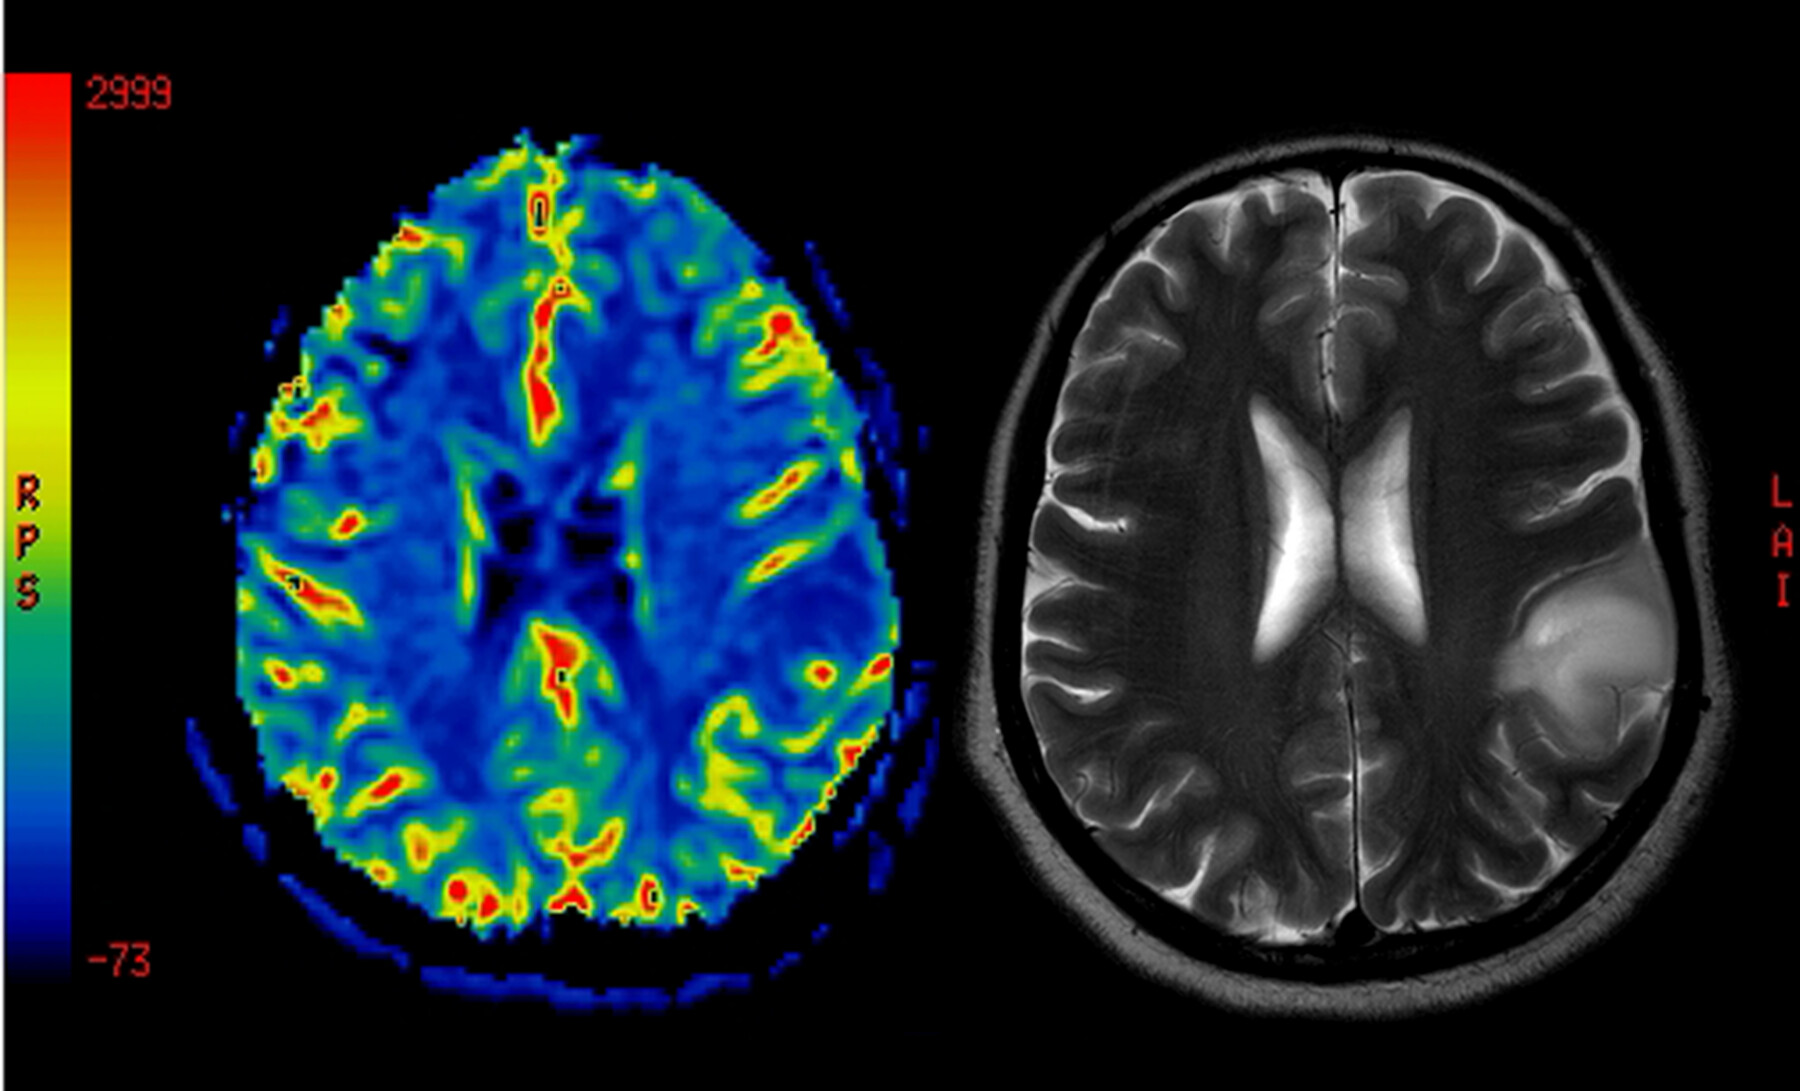

In the new analysis, researchers examined microglial inflammatory activity using the PET imaging tracer [18F]PBR06. Across the 10 patients, a total of 14 scans were collected before and after treatment.

Results showed that [18F]PBR06-PET scores decreased significantly with foralumab, indicating that the nasal therapy dampened the activity of microglia. A significant reduction in PET signals was observed as early as three months after treatment initiation, and levels continued to decline through the last follow-up assessment at a median of 7.5 months.

These changes showed strong correlations with PET imaging scores, meaning that higher reductions in [18F]PBR06-PET signals were significantly associated with greater decreases in inflammatory markers and increases in neuroprotective proteins.